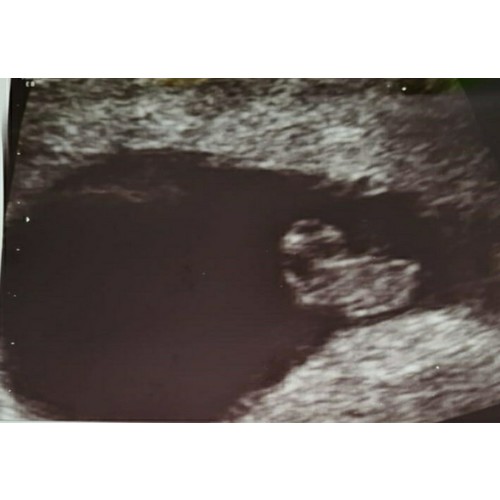

Vandaag met 9 weken 😁

Oh wauw wat een super mooie echo! Ik moet nog wachten tot bijna 9 weken voor de 1e echo 🙂